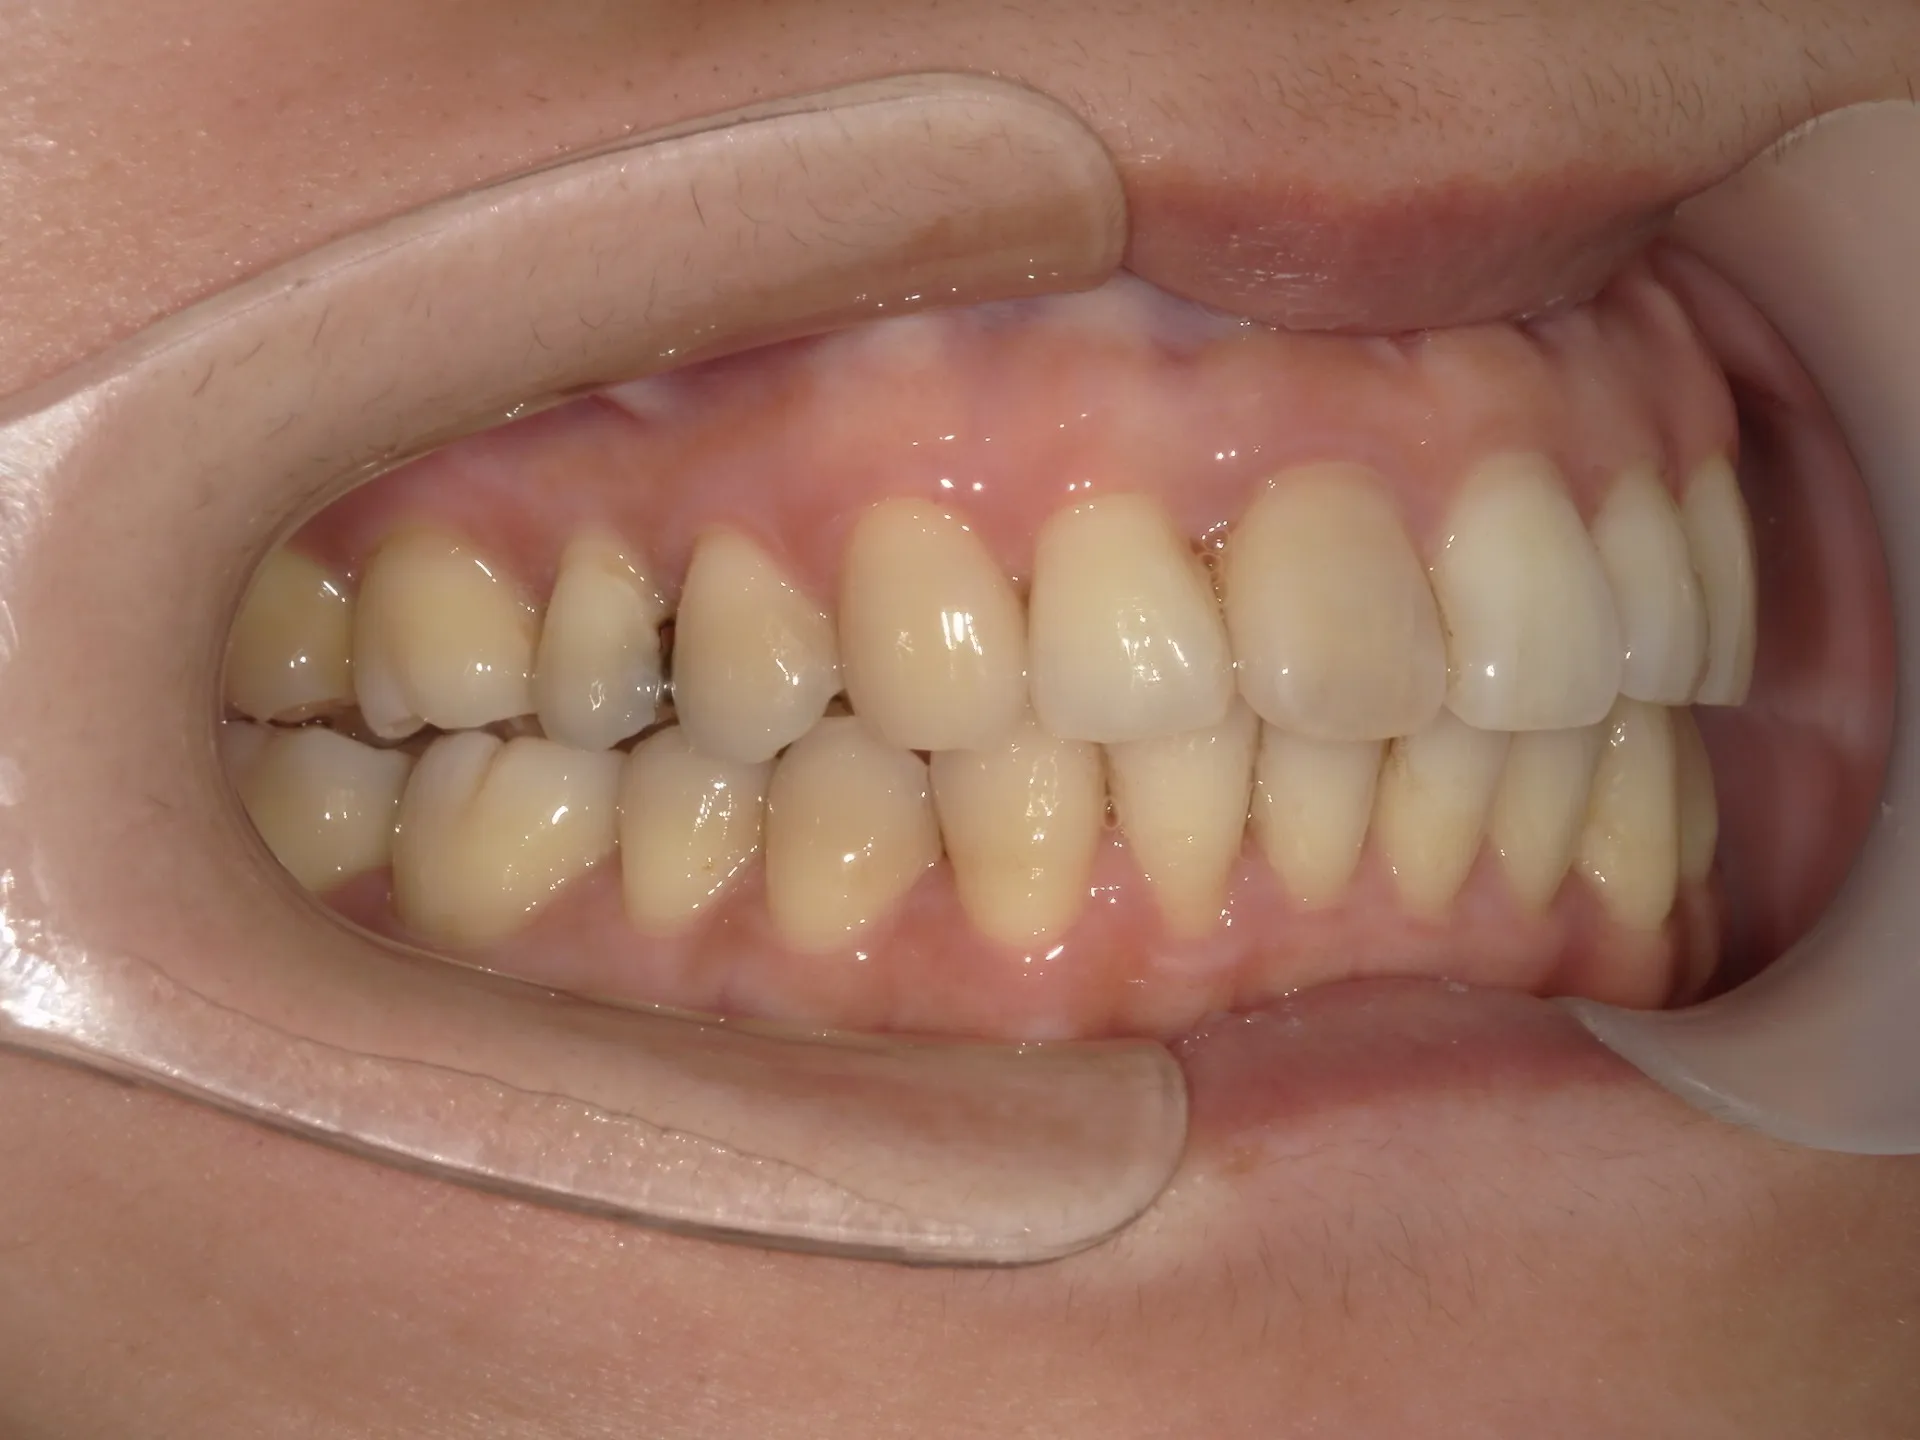

今回はねじれてしまった前歯の矯正治療をインビザラインというマウスピース矯正で治療した症例をご紹介いたします。